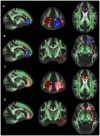

Alzheimeŕs disease (AD) represents the most prevalent neurodegenerative disorder that causes cognitive decline in old age. In its early stages, AD is associated with microstructural abnormalities in white matter (WM). In the current study, multiple indices of diffusion tensor imaging (DTI) and brain volumetric measurements were employed to comprehensively investigate the landscape of AD pathology. The sample comprised 58 individuals including cognitively normal subjects (controls), amnestic mild cognitive impairment (MCI) and AD patients. Relative to controls, both MCI and AD subjects showed widespread changes of anisotropic fraction (FA) in the corpus callosum, cingulate and uncinate fasciculus. Mean diffusivity and radial changes were also observed in AD patients in comparison with controls. After controlling for the gray matter atrophy the number of regions of significantly lower FA in AD patients relative to controls was decreased; nonetheless, unique areas of microstructural damage remained, e.g., the corpus callosum and uncinate fasciculus. Despite sample size limitations, the current results suggest that a combination of secondary and primary degeneration occurrs in MCI and AD, although the secondary degeneration appears to have a more critical role during the stages of disease involving dementia.